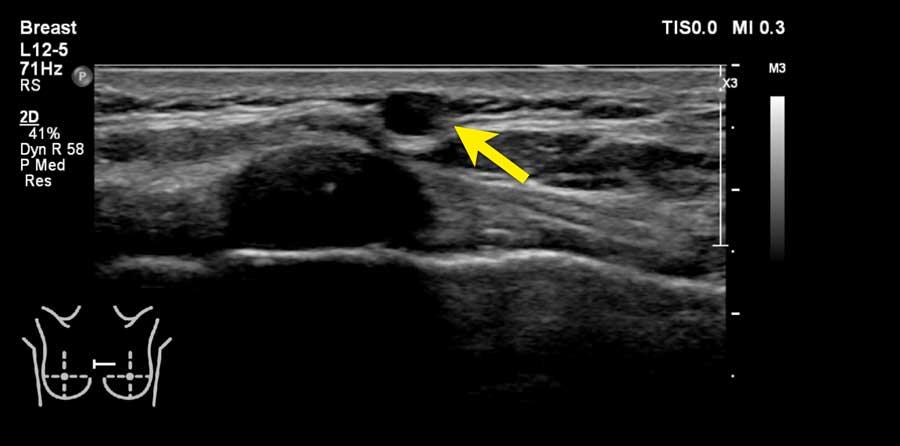

Đây là hình ảnh siêu âm bình thường của tuyến vú.

Lớp xám phía trên là da.

Tiếp theo là sự pha trộn giữa mô mỡ (tối hoặc giảm âm) và mô tuyến (xám sáng hoặc tăng âm).

Lớp có vân sọc phía sau mô vú là cơ ngực.

Phía sau hoặc sâu hơn so với xương sườn có một vùng đen hay bóng cản âm phía sau.

Phổi là lớp có thể quan sát sâu nhất.

Không khí trong phổi phản xạ hầu hết sóng âm, tạo ra một đường sáng hoặc tăng âm với bóng cản bẩn phía sau.